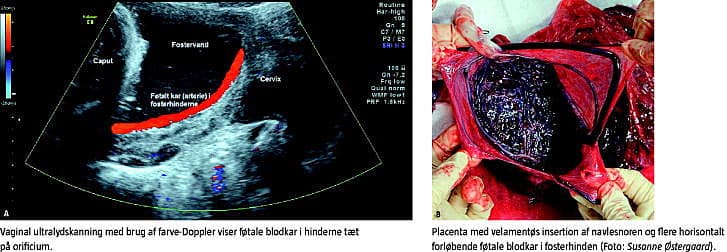

En 36-årig nullipara, gravid 33 uger + 5 dage kom til kontrol af placentas beliggenhed, idet man ved skanning i 20. uge havde fundet, at placenta dækkede orificium internum. Ved en ultralydskanning sås et normalvægtigt barn i hovedstilling. Placenta lå på bagvæggen, 22 mm fra orificium. Navlesnoren var velamentøst insereret, og der fandtes flere kar i hinderne tæt på orificium (A).

På baggrund af dette blev der foretaget elektivt sectio ved 36 uger + 0 dage. Barnet vejede 2.640 g og fik apgarscore 10/1 og 10/5. Ved undersøgelse af placenta og fosterhinder fandt man en velamentøs insereret navlesnor og føtale blodkar i hinderne over cervix, hvilket er foreneligt med vasa prævia (B).

Vasa prævia er en sjælden tilstand (1:2.500 fødsler), hvor føtale blodkar løber i hinderne over cervix. Prænatal diagnose er af største betydning, idet den perinatale mortalitet i udiagnosticerede tilfælde er rapporteret til at være 56%, mens overlevelsen er 97%, hvis diagnosen stilles prænatalt [1]. Diagnosen stilles ved ultralydskanning med farve-Doppler [2]. Forliggende placenta i andet trimester, velamentøs insertion af navlesnoren, biplacentae, in vitro-fertilisering og flerfoldsgraviditet disponerer til vasa prævia [3], hvorfor der bør udvises særlig opmærksomhed ved disse graviditeter.